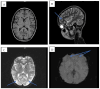

Scabies is a parasitic infestation of the skin with high prevalence in crowded spaces. In some instances, scabies becomes the underlying factor for complicated skin-borne opportunistic pathogens infections in both children and adults. Geographic area and socio-economic factors are determinants of the endemic pattern of this disease. Currently, the treatment of scabies has been under special attention. A combination of oral therapy with Ivermectin and sulfur-based ointments are the gold standard. However, caution is required in patients with kidney impairment. The renal involvement in children with scabies is mainly caused by acute glomerulonephritis. The severity of the nephritic syndrome can lead to other complications. Also, Ivermectin possesses a nephrotoxic effect. Severe hypertension can lead to neurological complications. The aim of our case report is to present two unusual complications in brothers with scabies. We report the cases of two brothers with scabies who presented with severe skin infection that developed acute post infectious glomerulonephritis (APIGN). In addition, one of the brothers presented with posterior reversible encephalopathy syndrome (PRES). The other one developed acute tubule-interstitial acute kidney injury following Ivermectin administration. The evolution of skin lesions was favorable, and kidney function returned to normal in both brothers.